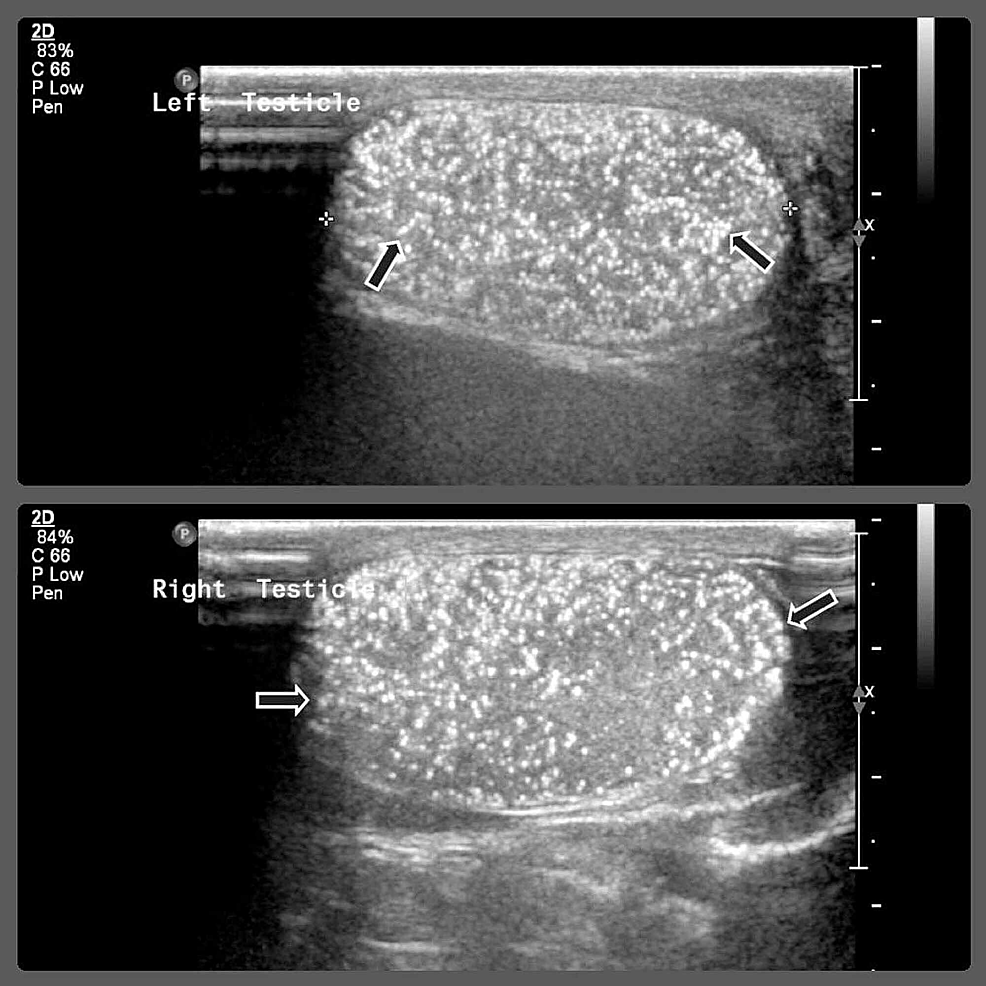

Cureus Mediastinal Germ Cell Tumor with Testicular Microlithiasis Testicular Cancer Germ Cell Testicular cancer is relatively rare compared with other cancer types, with an estimated 71 105 new cases worldwide in 2018 (< 1% of the male. Testicular germ cell tumors (tgct) can be diagnosed in every age group, but more than 90% of cases occur in young men. Germ cell tumors (gcts) account for 95 percent of testicular cancers (table 1).. Testicular Cancer Germ Cell.

RiT radiology Testicular Germcell Tumor Testicular Cancer Germ Cell Testicular tumors are the most common tumors in adolescent and young men and germ cell tumors (tgcts) account for most of all testicular. They may consist of one predominant histologic. There are two main types of gct: There are several differences between seminomas and nsgct, but the initial distinction is based on how the tumor looks under the microscope. These. Testicular Cancer Germ Cell.